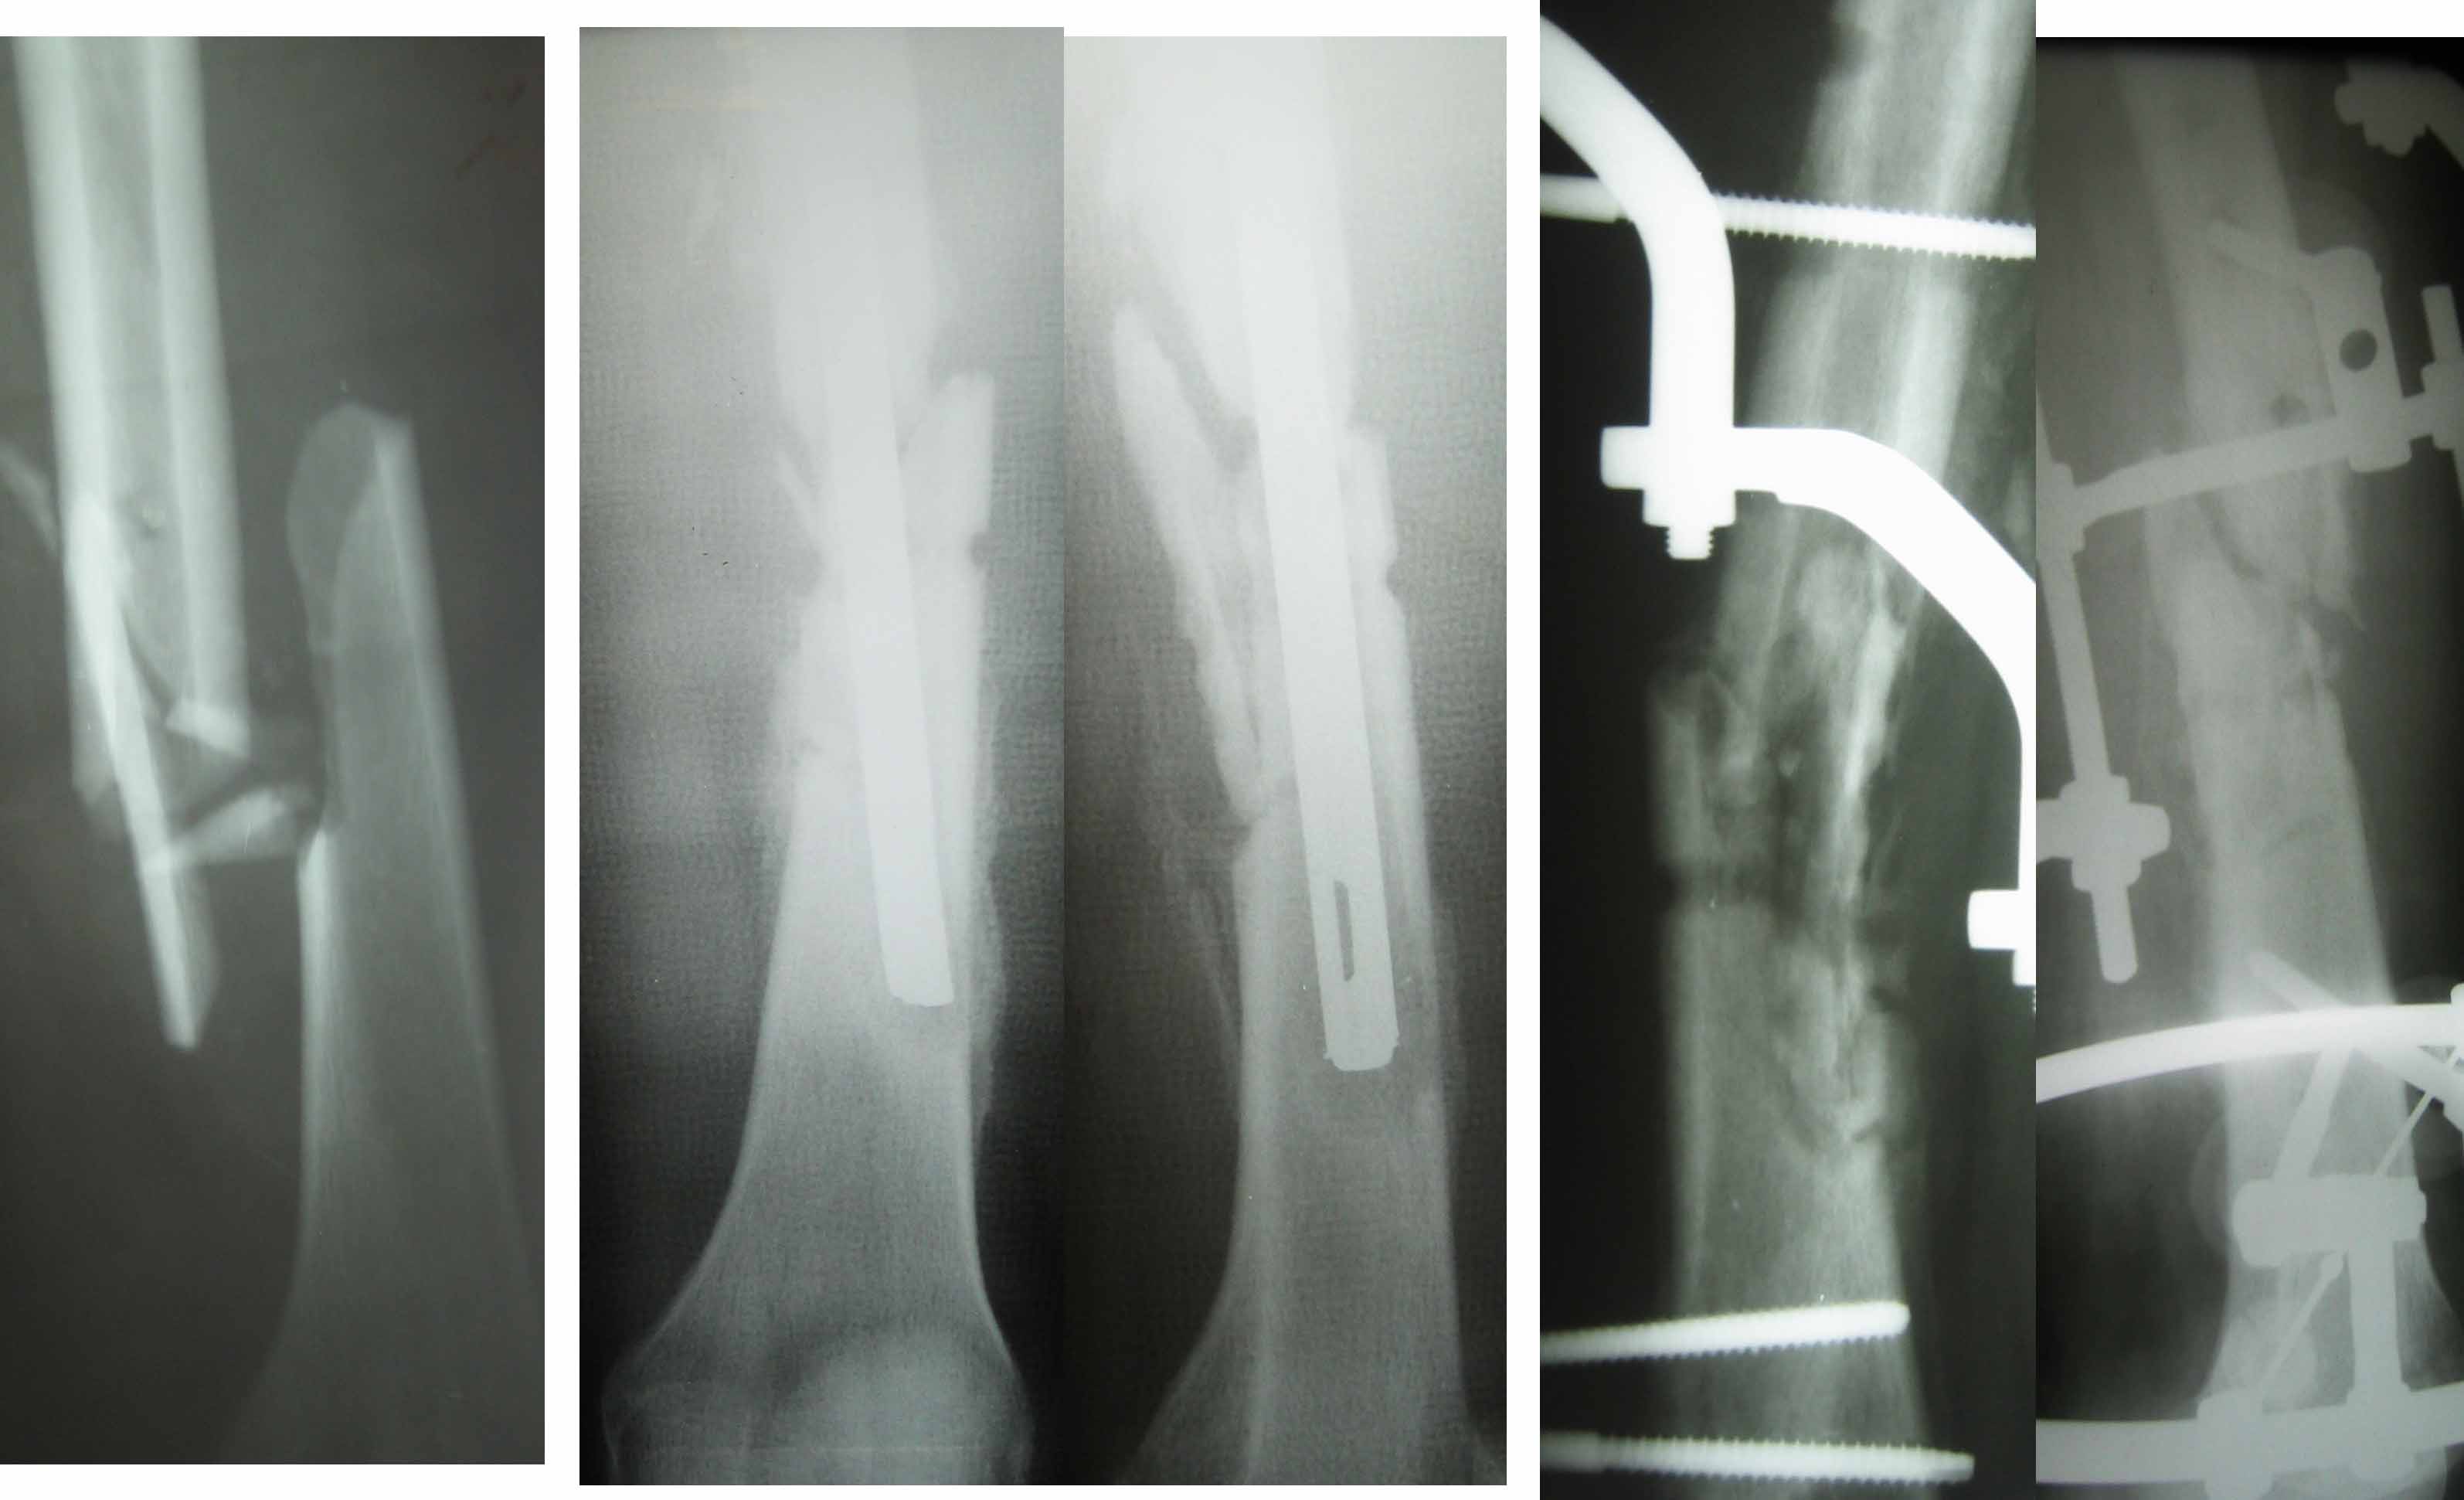

1. Перелом был закрытый оскольчатый, репозиция - открытая, первичный остеосинтез

-интрамедуллярный, нестабильный, дополненный кокситной повязкой.

Насколько стержень удален от коленного сустава, на столько же он и

выстоял из вертела - примерно на 8 см. Видимо, штифт заклинило в

проксимальном отломке при введении.

2. При отсутствии откровенных признаков инфекции (первичное заживление,

нормальная температура), и в то же время при такой "вуали" на

рентгенограммах (через 3 мес после операции) можно было предположить

наличие какого-либо, возможно, асептического вопспаления, связанного

с траматичностью открытой репозиции, обширным скелетированием

отломков, а также нестабильностью фиксации.

3. Извлечение штифта и переход на внешнюю фиксацию предполагал

создание компрессии, стабильной фиксации и, возможно, активизации

остеогенеза. В иные периоды казалось, что сращение происходит.

4. В настоящее время свищ закрылся, взятый из него неделей раньше

посев - стерильный. Температура - субфебрильная в середине дня. Вполне допустима мысль об инородном теле,

оставленном во время первой операции.

5. В ближайшие недели планируем с Павлом Ивановым пойти на операцию -

открытая ревизия, возможно, резекция кости и интрамедуллярный

остеосинтез с антибиотическим цементом.